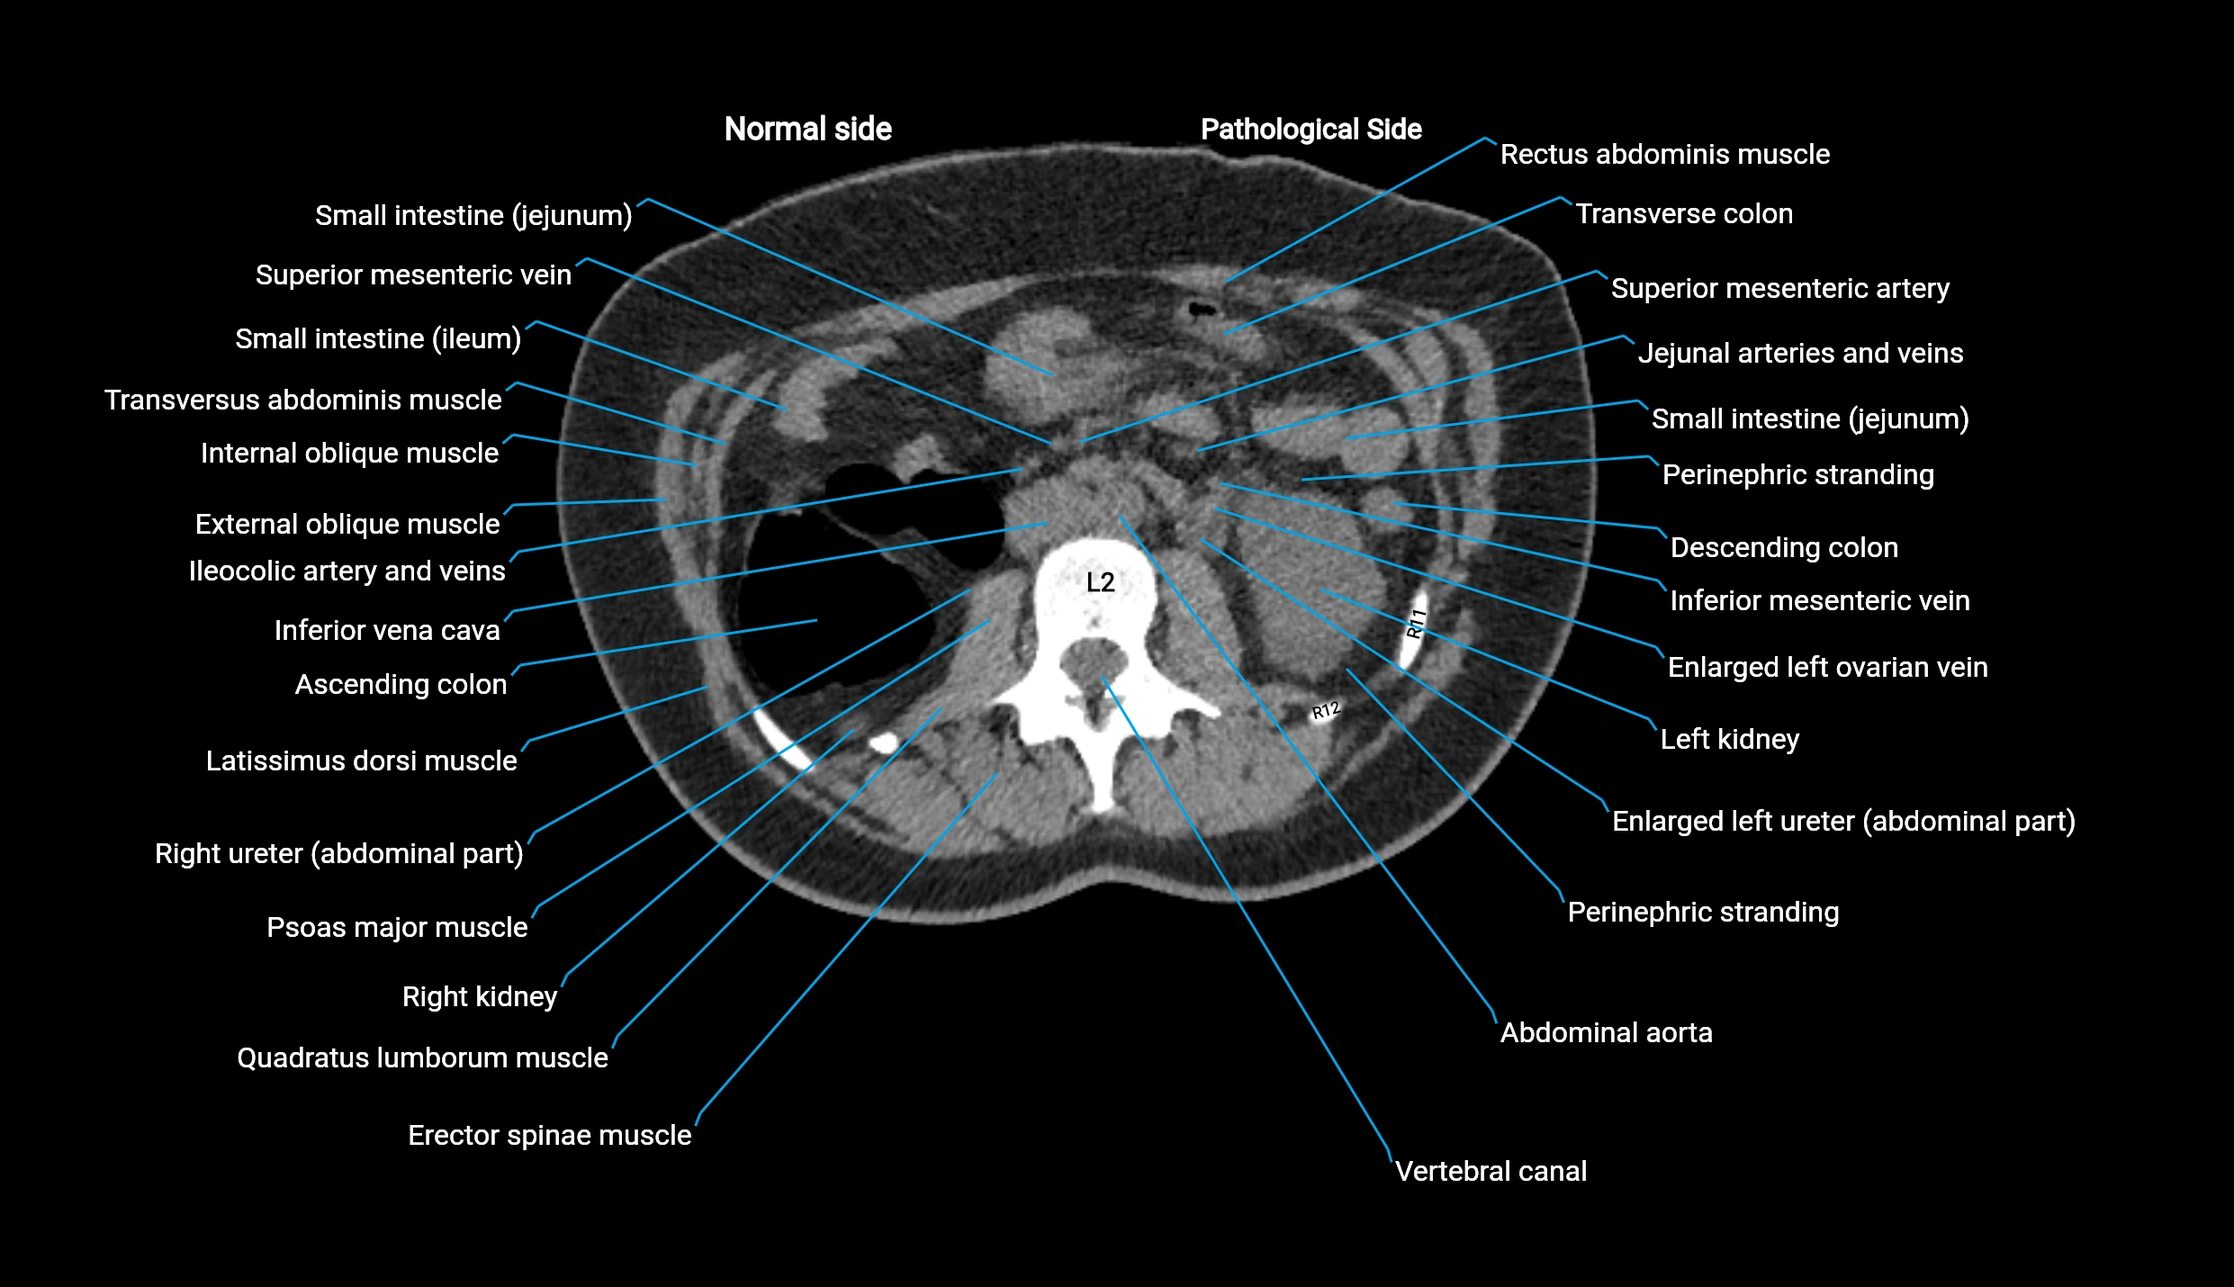

CT image

image